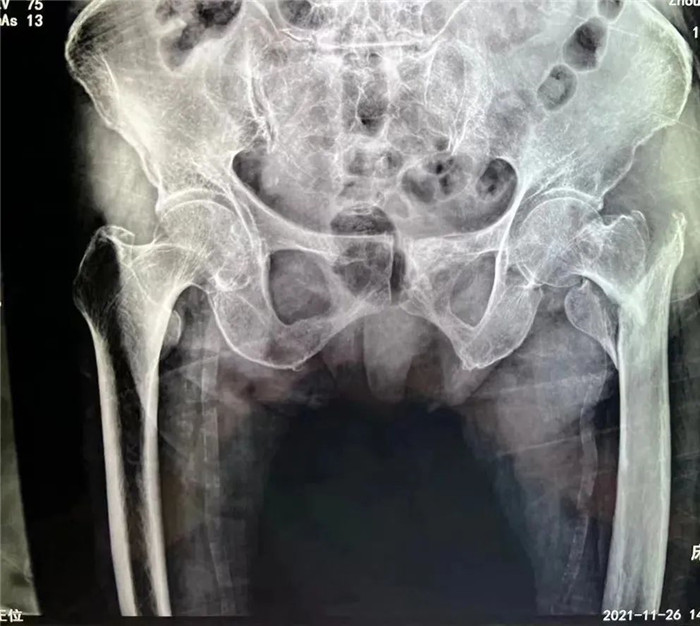

洪阿婆家住東港,前段時(shí)間在家行走時(shí)不慎摔倒,疼痛難忍,無法活動(dòng)。家人遂即送至我院,診斷為股骨粗隆粉碎性骨折。這是一種老年人常見的損傷,多是在摔倒時(shí)暴力導(dǎo)致股骨近端骨質(zhì)連續(xù)性斷裂,造成骨折。但是因老人年事已高,同時(shí)伴有腦梗死、肺部感染等多種并發(fā)癥,無論采取保守治療還是手術(shù)治療,都存在一定風(fēng)險(xiǎn),聽到這話的家屬異常沉重。

在手術(shù)團(tuán)隊(duì)及患者家屬的大力支持下,羅軍主任團(tuán)隊(duì)為洪阿婆實(shí)施了閉合復(fù)位INTERTAN內(nèi)固定術(shù)。雖然手術(shù)風(fēng)險(xiǎn)較大,但憑借精湛的技術(shù)及豐富的臨床經(jīng)驗(yàn),手術(shù)十分成功而且僅僅用了1個(gè)小時(shí),術(shù)中出血不多,術(shù)后患者恢復(fù)得很好,第二天就可以在起床活動(dòng),極大的提高了患者的生活質(zhì)量,避免了長期臥床造成的并發(fā)癥。